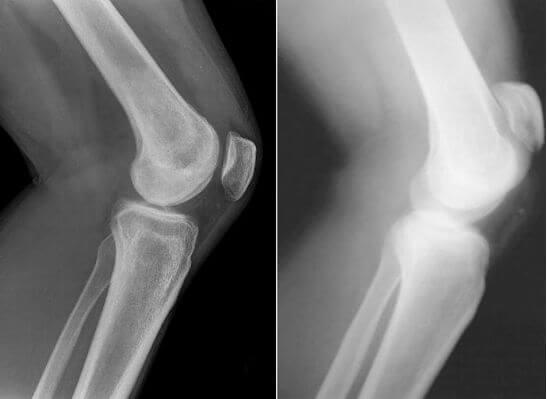

And here are pictures of joints before and after being treated with Maxiflex .

Woman. 54. The joint fully recovered.

Treatment period 1.5 months

Restoration of the elbow joint. Woman, 31. Maxiflex treatment duration - 2 months. The joint has fully recovered.

The photos clearly show that Maxiflex doesn’t just alleviate the pain,but also starts the processes of regeneration of the synovial fluid - the function chondroprotectors are meant to perform. As a result, the cartilage layer becomes wider and more elastic - the joint improves, pain and stiffness disappear.